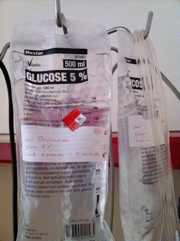

Zo een douche genomen met desinfecterende shampo. Nu lekker bakje koffie, glaasje choco en TV kijken. Ik krijg nu alvast een voorbereiding voor een infuus mbt het regulieren van de glucose. Wat een grote spuit….hahahaha Deze gaat er vannacht weer af en wordt er een dopje op geplaatst. Ik lig nu op een matras dat is gevuld met lucht.

Zo een douche genomen met desinfecterende shampo. Nu lekker bakje koffie, glaasje choco en TV kijken. Ik krijg nu alvast een voorbereiding voor een infuus mbt het regulieren van de glucose. Wat een grote spuit….hahahaha Deze gaat er vannacht weer af en wordt er een dopje op geplaatst. Ik lig nu op een matras dat is gevuld met lucht.Planning operatie